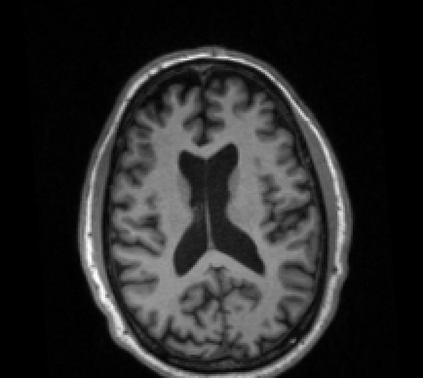

Due to various physical degradation factors and limited counts received, PET image quality needs further improvements. The denoising diffusion probabilistic models (DDPM) are distribution learning-based models, which try to transform a normal distribution into a specific data distribution based on iterative refinements. In this work, we proposed and evaluated different DDPM-based methods for PET image denoising. Under the DDPM framework, one way to perform PET image denoising is to provide the PET image and/or the prior image as the network input. Another way is to supply the prior image as the input with the PET image included in the refinement steps, which can fit for scenarios of different noise levels. 120 18F-FDG datasets and 140 18F-MK-6240 datasets were utilized to evaluate the proposed DDPM-based methods. Quantification show that the DDPM-based frameworks with PET information included can generate better results than the nonlocal mean and Unet-based denoising methods. Adding additional MR prior in the model can help achieve better performance and further reduce the uncertainty during image denoising. Solely relying on MR prior while ignoring the PET information can result in large bias. Regional and surface quantification shows that employing MR prior as the network input while embedding PET image as a data-consistency constraint during inference can achieve the best performance. In summary, DDPM-based PET image denoising is a flexible framework, which can efficiently utilize prior information and achieve better performance than the nonlocal mean and Unet-based denoising methods.